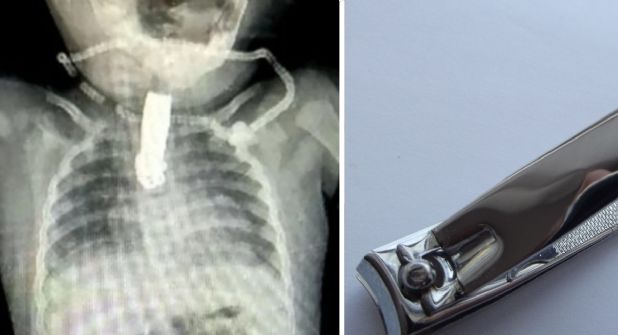

Su padres, al ver que la bebé tenía problemas al respirar, la llevaron de inmediato al hospital para su atención. Ya en el lugar se le realizó una radiografía, donde se reveló la existencia del objeto de cinco centímetros. Ante esto, los médicos dispusieron de una cirugía menor para extraerlo.